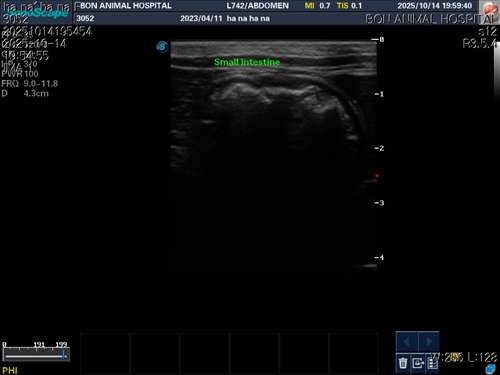

10월 10일 포도를 토해논후로 식욕저하 기력저하가 있어서 동물병원에 방문해서 엑스레이를 찍었는데 우선 지켜보자는 말과 소화제처방과 주사를 맞고 집왔습니다 그 후로도 안먹어서 12일에 동물병원에가서 혈액검사도 하고 수액도 맞았습니다 췌장쪽 수치가 좀 높아서 췌장쪽만 다시 검사했는데 수치는 괜찮았습니다 식욕촉진이랑 소화제처방 받아서 먹이는데 식욕저하도 여전하고 기력이 좀 없고 10일부터 14일까지 대변을 못보고있어서 14일에 병원에 가서 엑스레이랑 초음파를 했는데 장폐색일수도 있다는 말을 들었습니다 초음파상으로는 소장쪽 이물이 의심된다고 하셨어요ㅠ